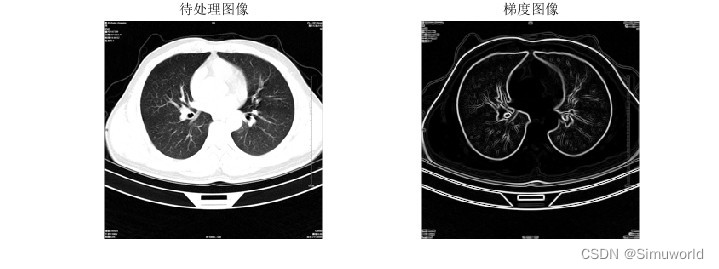

本文介绍了基于分水岭分割算法的肺癌诊断系统,通过MATLAB进行仿真。首先,对CT图像进行预处理,然后运用分水岭算法进行分割,提取肺部区域。接着,通过特征提取和机器学习分类实现肺癌的自动诊断。算法原理包括图像平滑、梯度计算、形态学处理和分水岭变换。